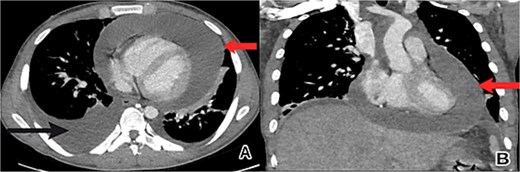

The patient’s condition worsened, developing a high fever, rapid breathing, and low blood pressure, leading to admission to the intensive care unit and treatment with medications to raise blood pressure. A full infection workup was negative. A computed tomography (CT) scan of the chest showed a large pericardial effusion measuring 5.5 cm in thickness and a small right heart chamber (Fig. 2). An echocardiogram revealed a normal left ventricle with an ejection fraction of 60%, but the right ventricle was compressed by a large oval-shaped structure inside the pericardial sac. The pericardial effusion measured 4.6 cm in thickness, and the inferior vena cava was dilated at 2.7 cm, with no heart valve regurgitation or blood clots inside the heart (Fig. 3).

Chest CT scan showed a large pericardial effusion. (A) An axial view revealed a pericardial effusion (indicated by the upper arrow) and a right-sided pleural effusion (lower arrow). (B) A coronal view revealed a pericardial effusion (arrow) with small right heart chambers.